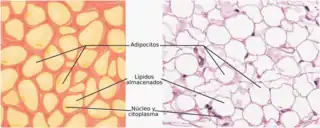

El tejido adiposo o tejido graso es el tejido de origen mesenquimal (un tipo de tejido conjuntivo) conformado por la asociación de células que acumulan lípidos en su citoplasma: los adipocitos.

Morfología de tres clases diferentes de adipocitos. | ||

El citosol y el núcleo quedan reducidos a una pequeña área cerca de la membrana. El resto es ocupado por una gran gota de grasa. El tejido adiposo, que carece de sustancia fundamental, se halla dividido por finas trabéculas de tejido fascicular en lóbulos.